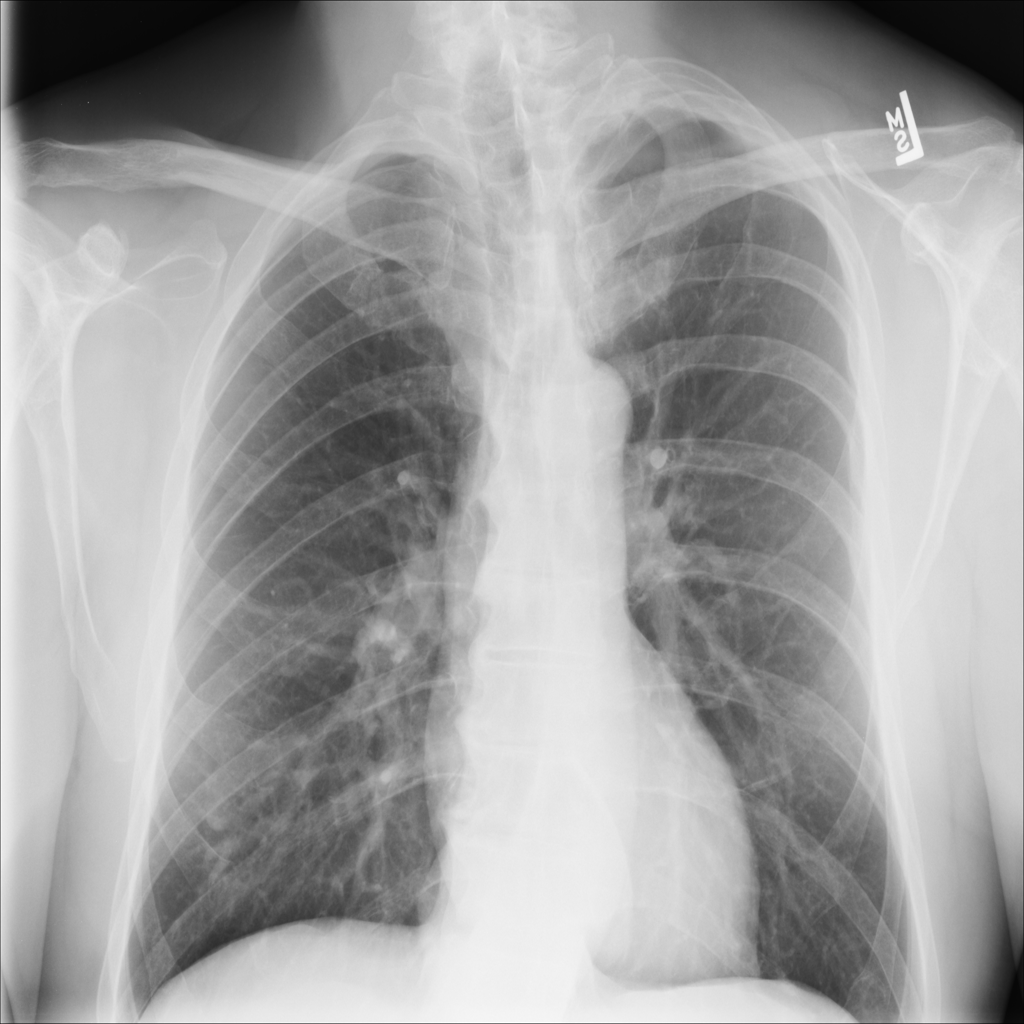

Showing up to 90 reference images for Hernia.

PAT-0ABD · IMG-000Hernia

PAT-0ABD · IMG-000

PA